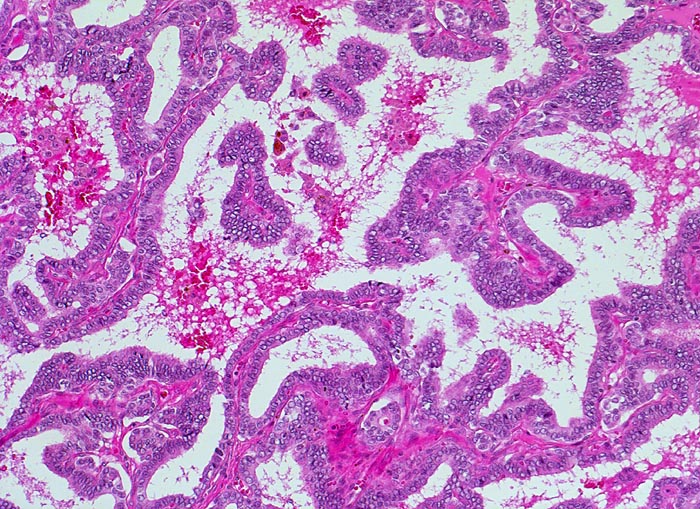

PathoPic ID 4736 - papilläres Schilddrüsenkarzinom

papilläres Schilddrüsenkarzinom

maligner Tumor

Schilddrüse

Endokrinium

Papillärer Tumor.

In der Feinnadelpunktion eines 2cm grossen kalten Knotens werden Karzinomzellen nachgewiesen vereinbar mit einem papillären Schilddrüsenkarzinom.

Histologie

100

46